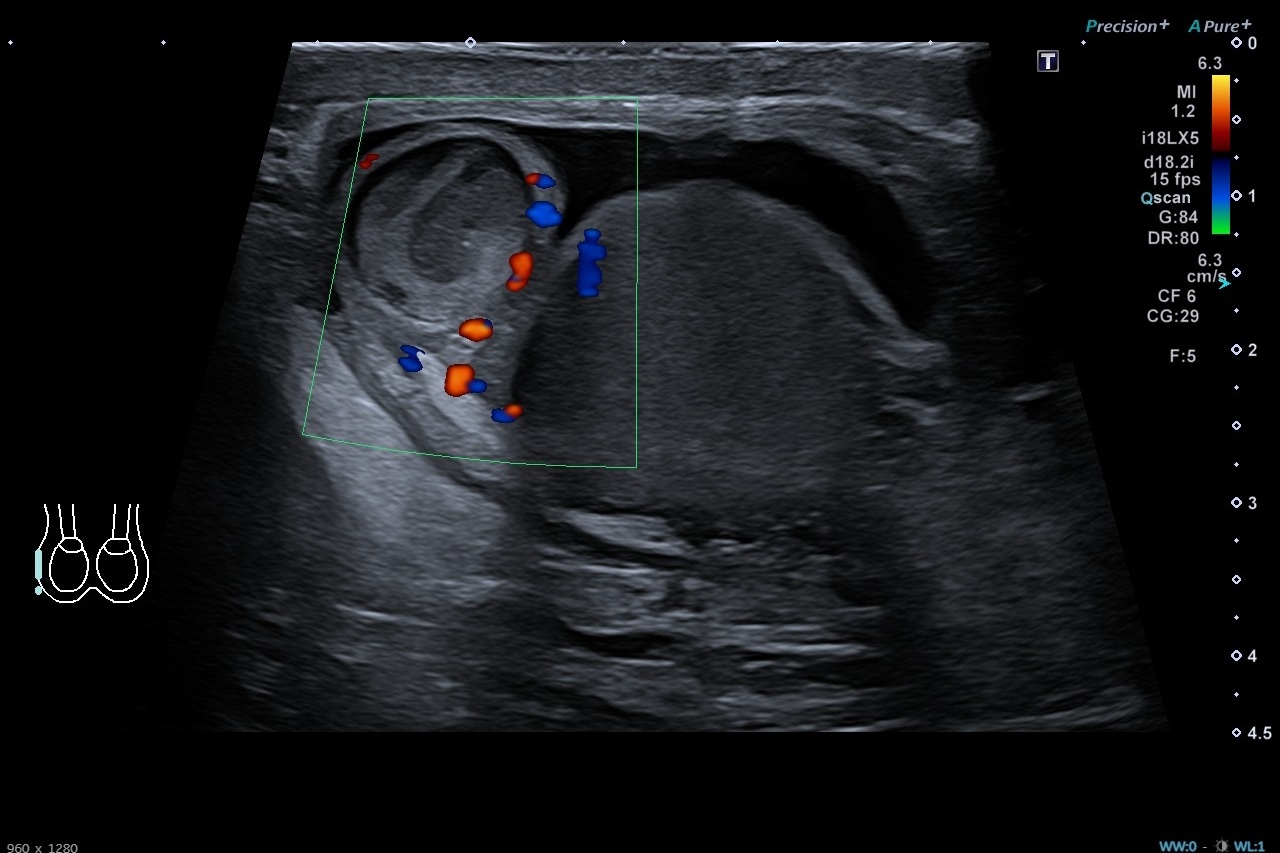

Pruebas complementarias: Sistemático de orina negativo. Ecografía escrotal: Testículos, epidídimos y cordones espermáticos de tamaño, morfología y ecogenicidad normales. Doppler normal en ambos testículos. Adyacente al polo superior del testículo derecho se identifica una estructura redondeada de unos 13 x 12 mms de ecogenicidad heterogénea, sin captación Doppler interna. Es sugestivo de torsión de hidátide de Morgagni, a correlacionar con evolución clínica. No hay datos de torsión testicular. Presencia de moderado hidrocele de aspecto reactivo.